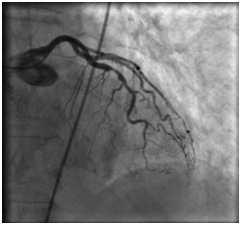

Для визуализации атеросклеротических бляшек по показаниям применяется ангиография – рентгенологическое исследование с введением контрастного вещества. В случае подготовки к операции на сосудах сердца выполняется коронароангиография.

18.08.2011 выполнена селективная коронарная ангиография.

Огибающая коронарная артерия без признаков стенозирующего атеросклероза.

Правая коронарная артерия – в средней трети стеноз 70%. Правый тип коронарного кровообращения.

Передняя межжелудочковая артерия

Правая коронарная артерия

18.08.2011 интервенционным кардиохирургом в область стеноза проксимальной трети передней межжелудочковой артерии проведен баллонный катетер со стентом «Мульти-линк 8» размерами 3×12 мм, произведена имплантация.

В дистальную часть правой коронарной артерии проведен проводник 0,014″. В область стеноза проведен баллонный катетер со стентом «Мульти-линк 8» размерами 3×12 мм, произведена имплантация.

На контрольных ангиограммах получен хороший кровоток

Довольно просто оценить наличие атеросклеротических бляшек и в сосудах ног. Это делается с помощью того же ультразвукового метода. Бляшки, находящиеся в сосудах сердца, увидеть сложнее. Однако для принятия решения о лечении имеют значение только те бляшки в коронарных сосудах, которые значительно перекрывают кровоток, вызывая симптомы — в случае хронического поражения этих сосудов речь идет о «стенокардии напряжения», которую выявляют путем анализа имеющихся клинических проявлений (в типичном случае это боль или дискомфорт в грудной клетке, возникающие при ходьбе, беге или поднятии тяжести и проходящие за несколько минут в покое) и выполнением исследования с физической нагрузкой в ходе которого регистрируют электрокардиограмму, эхокардиограмму или сцинтиграфическое изображение сердца с целью выявить объективные признаки ишемии, т. е. временного несоответствия между доставкой крови к миокарду и потребностей в ней при нагрузке. В случаях, когда врач решает, что имеются показания для проведения операции на сосудах сердца, выполняют коронароангиографию — рентгенологическое исследование сосудов сердца с введением контрастного вещества, в ходе чего можно непосредственно увидеть просвет сосудов сердца и имеющиеся в этих сосудах сужения, с целью наметить план операции и выбрать ее вариант. [8]